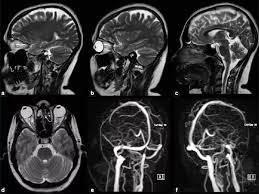

По сообщению интернет издания Ancient Origins, ученым удалось провести уникальное исследование костной ткани внутреннего уха обезьяны с помощью компьютерной 3D томографии.

"Полукружные каналы, находящиеся в черепе между нашим мозгом и ухом, имеют решающее значение для обеспечения нашего ощущения равновесия и положения тела во время движения. Они обеспечивают фундаментальный компонент нашего передвижения, о котором большинство людей, скорее всего, не догадывается", - объясняет Инан Чжан, аспирант Института палеологии и палеоантропологии позвоночных Китайской академии наук и ведущий автор статьи, опубликованной в журнале Инновация.

Впервые черепа люфенгпитеков были обнаружены в Китайской провинции Юньнань в начале 1980-х годов. В то время сильная деформация черепов скрыла костную область уха, поэтому это помешало исследованиям на долгие годы.

Современные ученые из IVPP и Юньнасского института реликвий и археологии (YICRA) использовали новейшие технологии трехмерного сканирования для создания виртуальной реконструкции черепов. Полученные сканы сравнили со сканами, собранными у других животных и доисторических обезьян и людей из Азии, Европы и Африки. Результатом анализа стала возможность провести уже доказанную параллель между особенностями тела люфенгпитеков и современного человека.